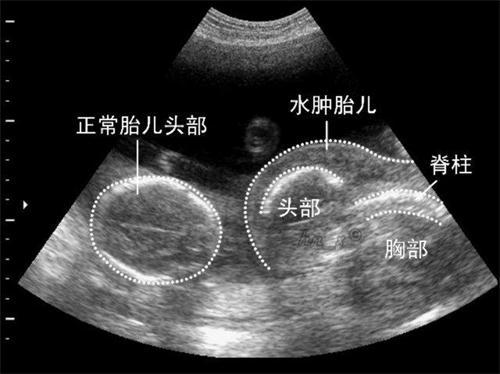

张女士在其怀孕四个月的时分做了一次B超,B超的结果让她又难过又伤心,由于很不幸,腹中的宝宝被诊断出是畸形,身体比例不和谐。医生一开端恳求做羊水穿刺,可是得知有风险后张女士选择了过两个月再做一次B超看看。

在怀孕6个月的时分张女士又带着忐忑的心情去到医院做了一次B超。可是结果依旧如第一次一样,医生还是判别宝宝为畸形胎,宝宝身体比例不和谐。张女士依旧不愿置信的问医生结果肯定嘛?得知医生非常肯定的态度张女士的脑子里一下就炸开了锅?怎样会这样,老天对我真狠啊。等张女士缓过来的之后,张女士依旧不愿置信自己的宝宝是畸形,孩子一定没问题的。分开的时分张女士又问了医生一遍这个就没有误诊的情况嘛?医生通知她也有这样的情况,只是很少很少,普通是没错的。

到了怀孕8个月的时分张女士又再一次的去做了B超,结果并没有发作改动,不过张女士也没有灰心,继续坚持要生下来。预产期很快就到来了,说到剖腹产张女士没有任何犹疑,很快就进了产房。一阵呱呱声宝宝出生了,当医生把孩子准备抱给张女士时,医生问我喜欢男的还是喜欢女的,张女士说喜欢女的,医生一声恭喜的说“7斤一两的安康公主,恭喜了。”只需宝宝安康男女关于张女士来说都一样。